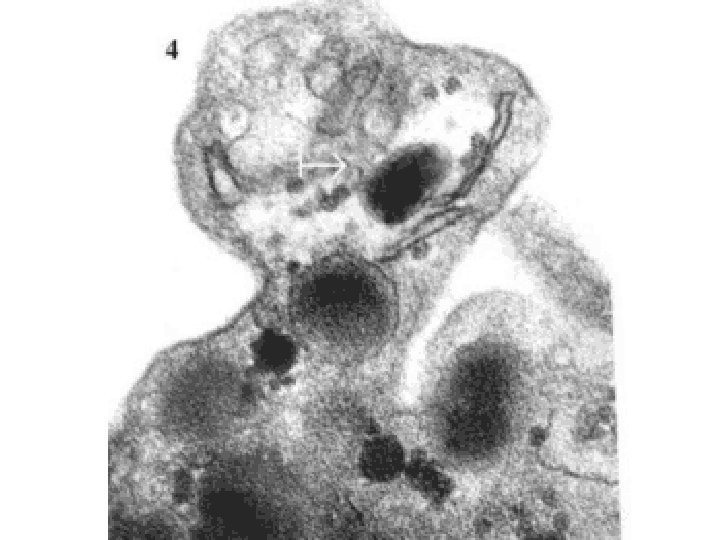

NORMAL platelet on LEFT, “DEGRANULATING” ALPHA GRANULE ON RIGHT AT OPEN WHITE ARROW

PLATELETS • ALPHA GRANULES – Fibrinogen – Fibronectin, a big CAM – Factor-V, Factor-VIII – Platelet factor 4 (anti-), TGF-beta • DELTA GRANULES (DENSE BODIES) – ADP/ATP, Ca+, Histamine, Serotonin, Epineph. • With endothelium, form TISSUE FACTOR

PLATELET PHASES • ADHESION • SECRETION (i. e. , “release” or “activation” or “degranulation”) • AGGREGATION

PLATELET ADHESION • Primarily to the subendothelial ECM • Regulated by v. WF, which bridges platelet surface receptors to ECM collagen

PLATELET SECRETION • BOTH granules, α and δ • Binding of agonists to platelet surface receptors AND intracellular protein “PHOSPHORYLATION”

PLATELET AGGREGATION • ADP • Tx. A 2 (Thromboxane A 2) (prothrombotic) • THROMBIN from coagulation cascade also • FIBRIN further strengthens and hardens and contracts the platelet plug